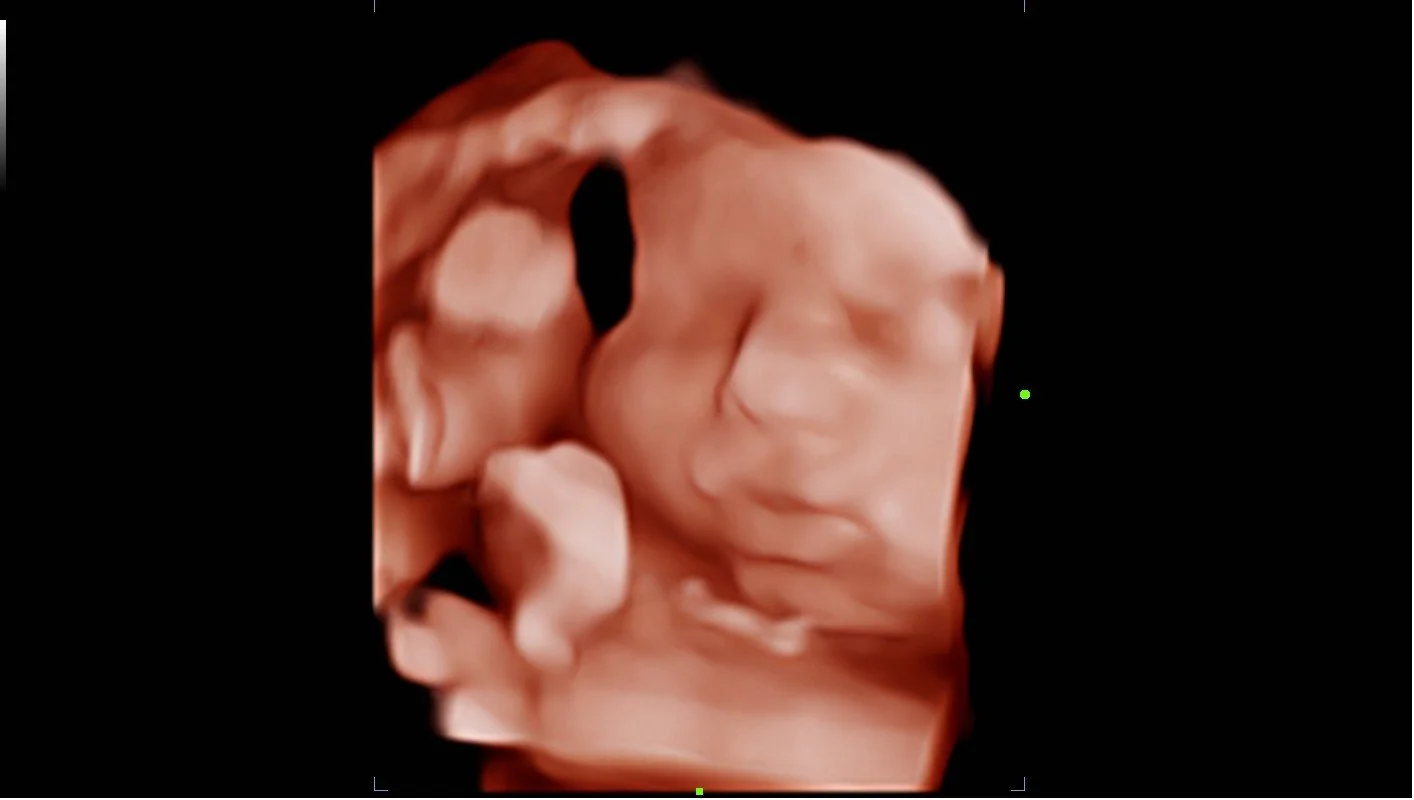

Welcome to our gallery of growing miracles. Here, you’ll find some of the beautiful moments families have shared with us — tiny profiles, sweet yawns, precious stretches, and those unforgettable first glimpses. Every image reflects a unique story of love, anticipation, and the incredible journey of parenthood. We’re honored to be part of these memories and can’t wait to capture yours, too.